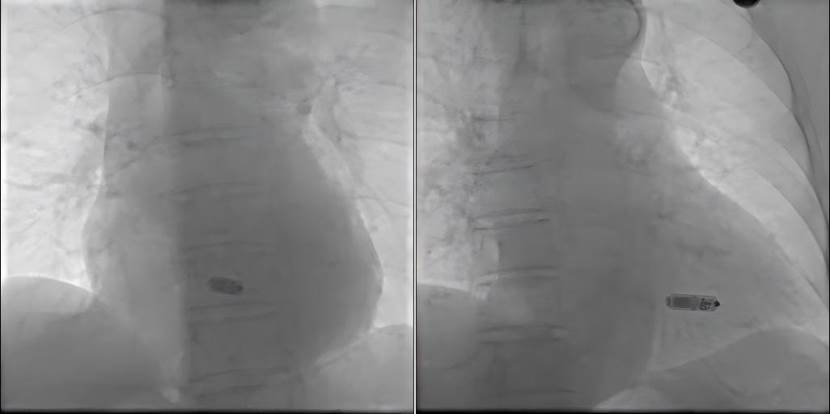

面对这一挑战,心血管内科李招兵主任团队经过严谨术前评估并与其家属充分沟通,决定采用国际前沿的Micra无导线起搏器。李招兵介绍:“Micra起搏器仅有一颗维生素胶囊大小,重量约2克,是目前全球领先的微型心脏起搏器。它通过微创方式,经右股静脉穿刺,借助特制的递送系统,直接植入患者右心室间隔部,全程无需切开皮肤制作囊袋,也无需放置导线,体表无任何疤痕,极大降低了手术创伤和感染风险,特别适合高龄、体弱的患者。”

10月8日,在介入导管室的紧密配合下,李招兵主任与谭剑凯医生组成的手术团队成功为患者实施了无导线起搏器植入术,手术在半小时完成,无导线起搏器各项参数及AV同步性良好。